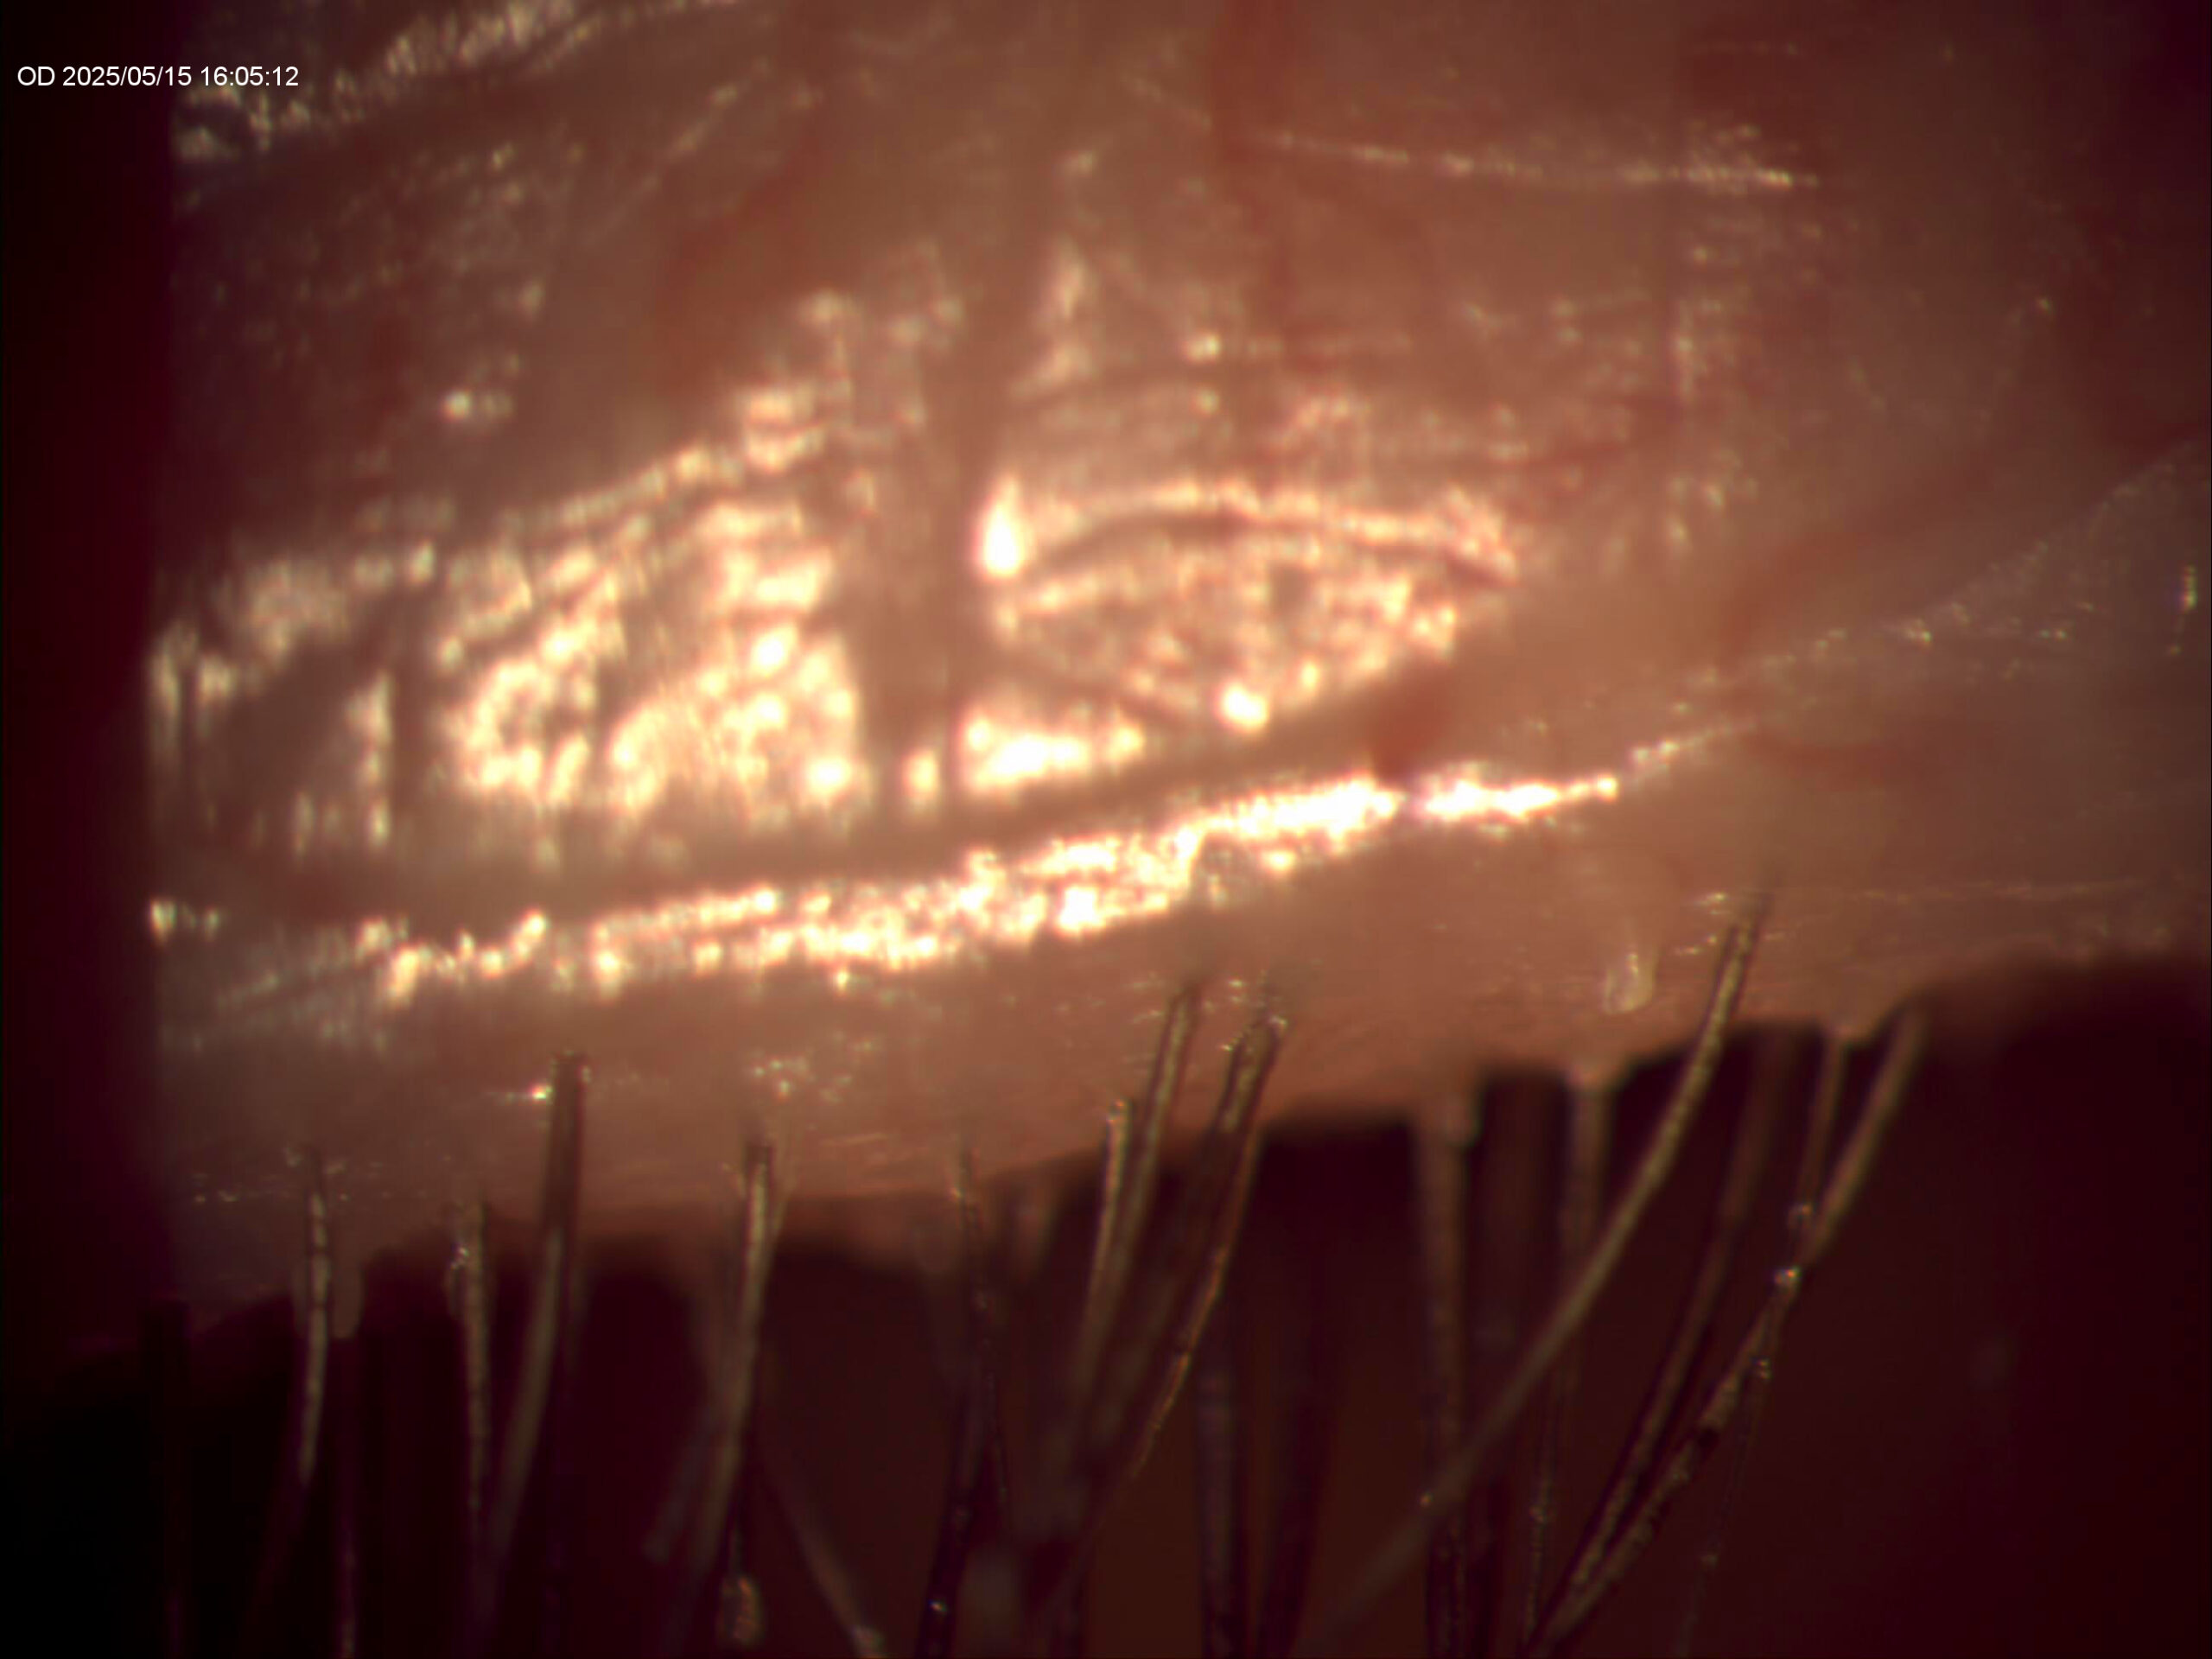

Grade2-B4Nulids-68WF

5minLater-AfterNuLids-68WF

NuLids-Demodex-Before&After (1)